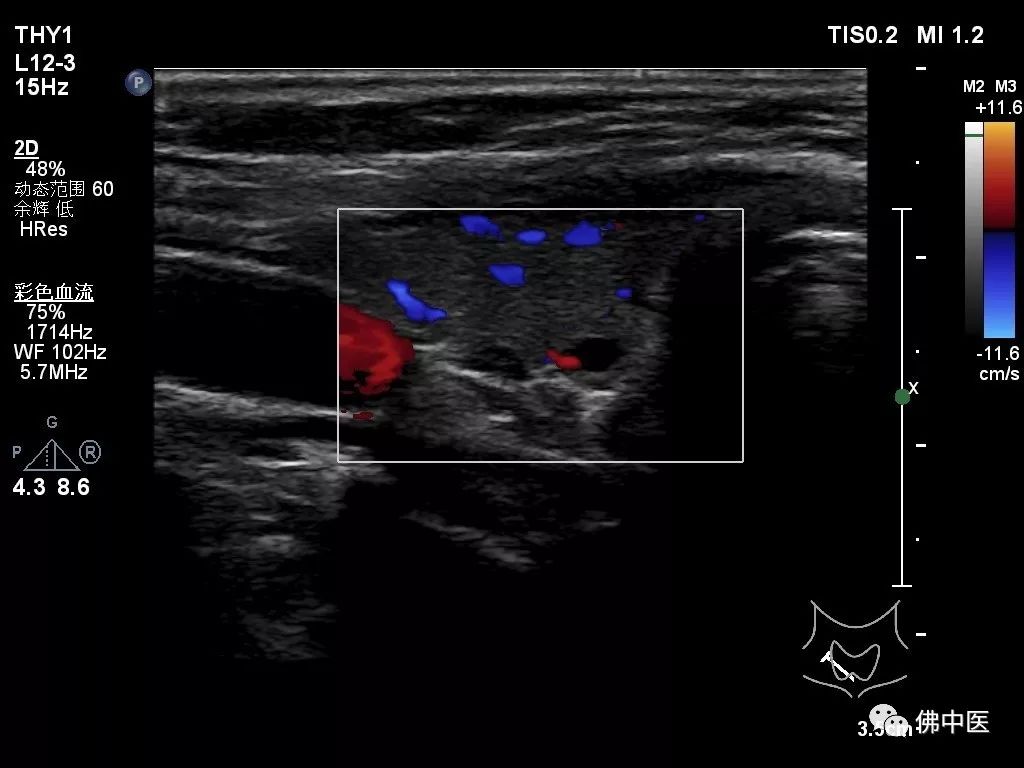

两名患者入院后住院生化检查提示碱性磷酸酶明显升高,血钙升高,但血磷下降,呈钙磷倒置现象,但肿瘤指标均未见明显异常;骨密度检查均提示“骨质疏松”;胸与双肺、全腹平扫+增强CT检查未见明显异常。针对此种具有恶性肿瘤征象,但无明确恶性肿瘤证据的患者,骨病专科主任劳永锵教授建议完善甲状腺彩超检查及甲状旁腺激素测定,结果两例患者甲状旁腺激素均明显升高,甲状腺彩超检查均可发现实性结节。

病例二(甲状腺彩超)